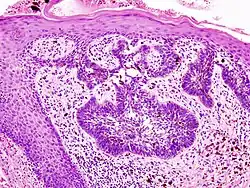

Basal cell carcinoma of the skin, cell nuclei (blue-purple), extracellular material (pink)

H&E is the combination of two histological stains: hematoxylin and eosin. The hematoxylin stains cell nuclei a purplish blue, and eosin stains the extracellular matrix and cytoplasm pink, with other structures taking on different shades, hues, and combinations of these colors.[5][6] Hence a pathologist can easily differentiate between the nuclear and cytoplasmic parts of a cell, and additionally, the overall patterns of coloration from the stain show the general layout and distribution of cells and provides a general overview of a tissue sample's structure.[7] Thus, pattern recognition, both by expert humans themselves and by software that aids those experts (in digital pathology), provides histologic information.

Hematoxylin principally colors the nuclei of cells blue or dark-purple,[6][15][14] along with a few other tissues, such as keratohyalin granules and calcified material. Eosin stains the cytoplasm and some other structures including extracellular matrix such as collagen[5][7][14] in up to five shades of pink.[8] The eosinophilic (substances that are stained by eosin)[5] structures are generally composed of intracellular or extracellular proteins. The Lewy bodies and Mallory bodies are examples of eosinophilic structures. Most of the cytoplasm is eosinophilic and is rendered pink.[10][15] Red blood cells are stained intensely red.